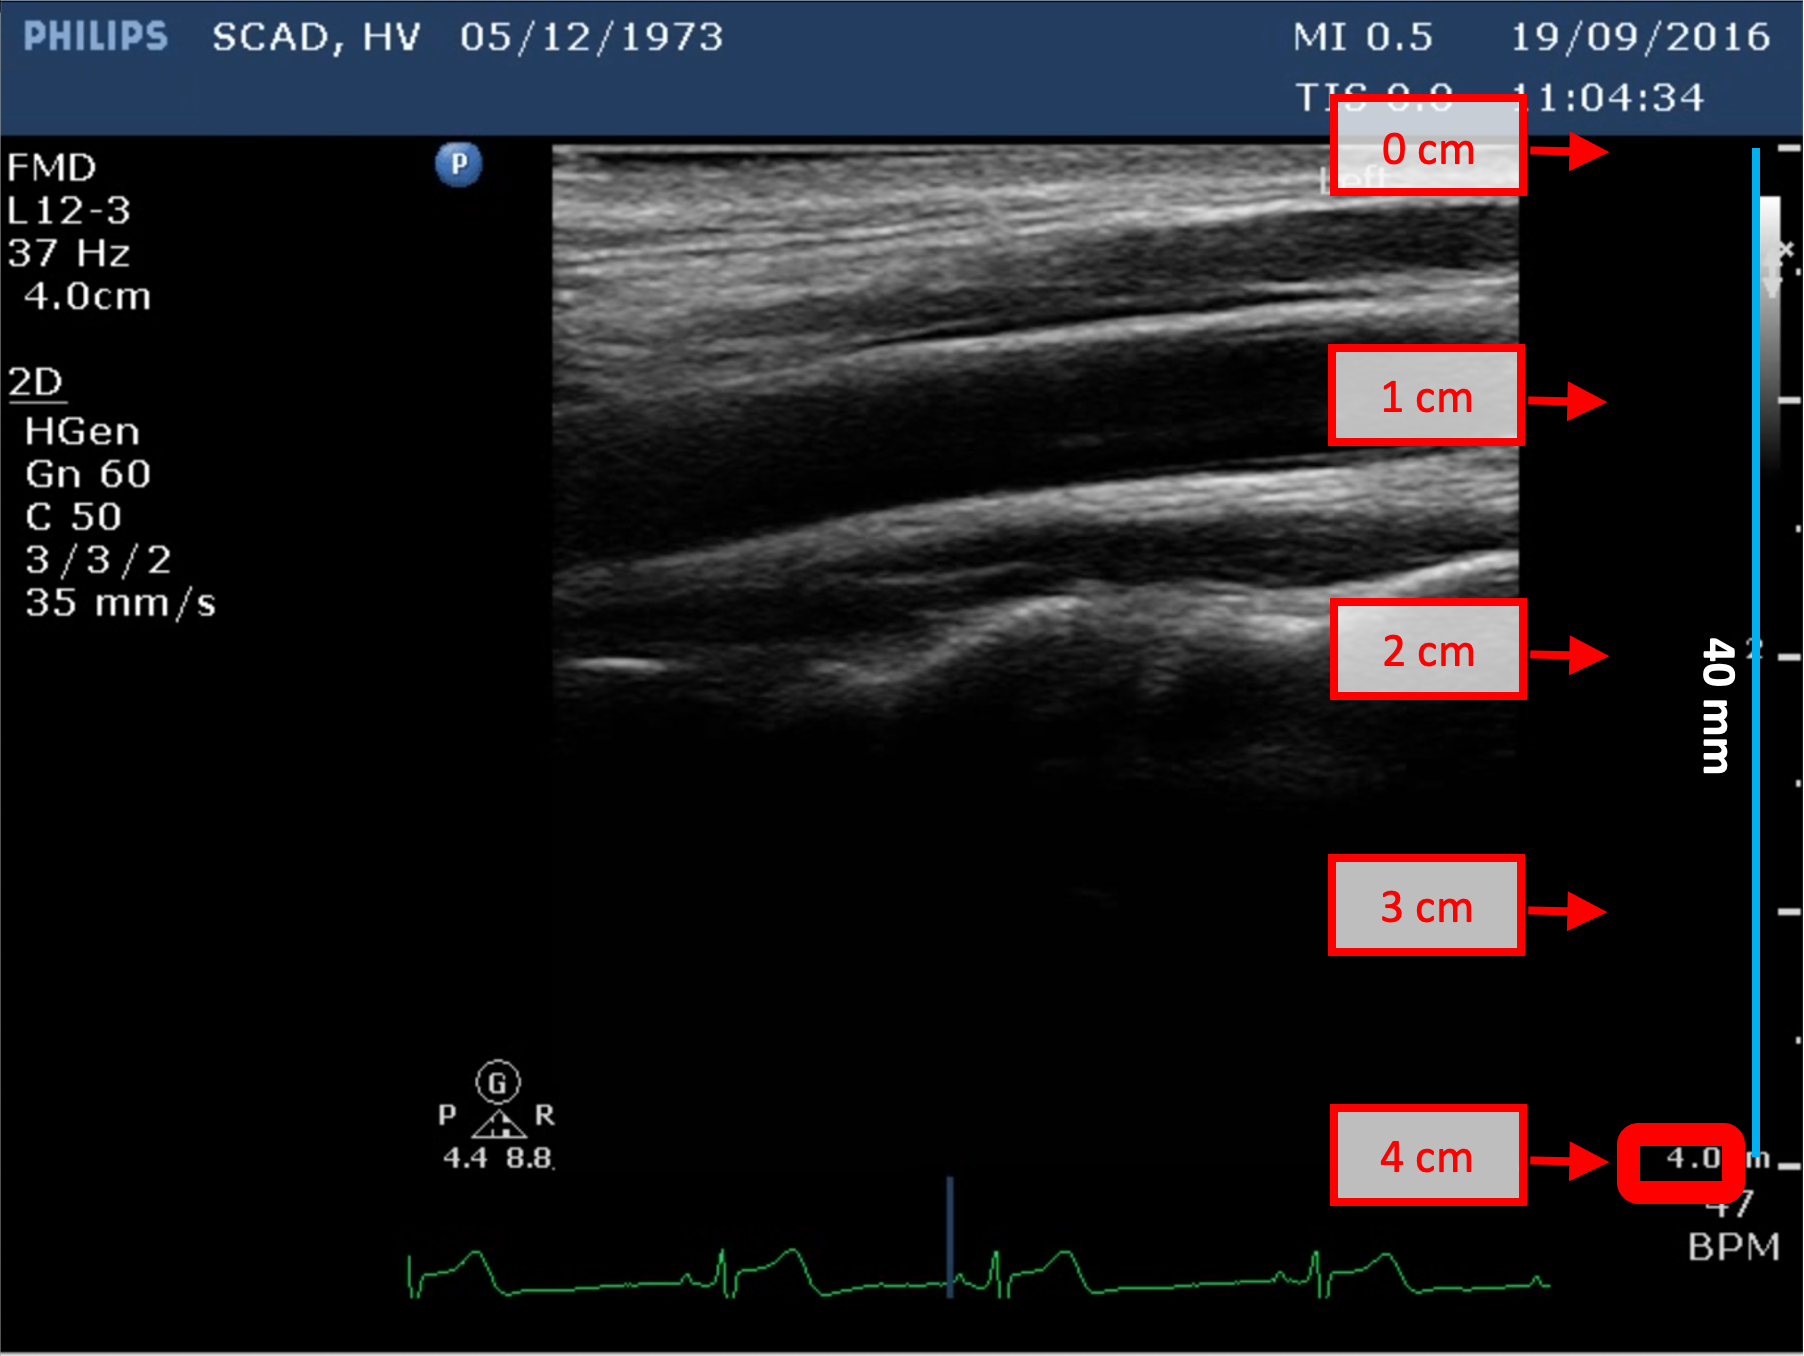

B-mode calibration examples

The following images show examples of calibrations of the b-mode image. Graphic items in red shows where you can find the information about the depth of the image in the ultrasound image.